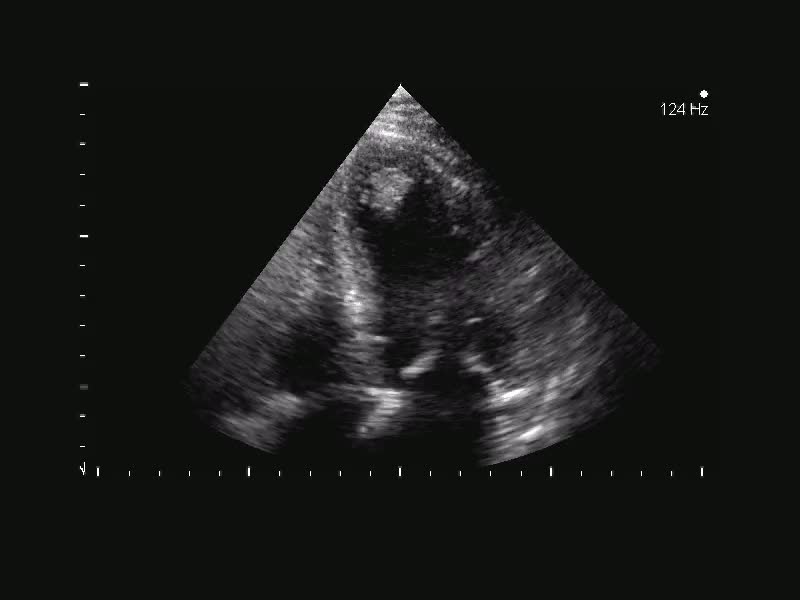

Titolo:

Autore: